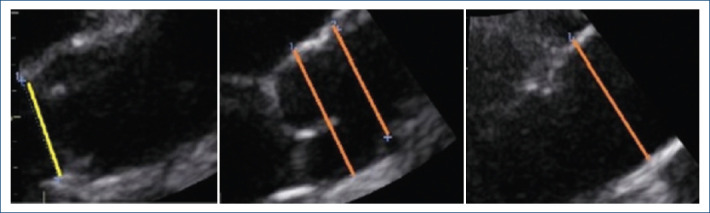

Materials and methods: Transthoracic echocardiograms were performed on all patients enrolled measuring aortic dimensions at six levels following the current standard recommendations. Absolute diameters and indexed diameters by body surface area (BSA) and height were compared between males and females.

Results: A total of 1,000 healthy adults were included, with an average age of 38.3 ± 12.7 years. Among them, 553 were females, and the majority were either Caucasian or Native American. Females exhibited lower values in all anthropometric parameters, echocardiographic measurements, and blood pressure. Analysis of aortic measurements revealed that females had lower absolute aortic diameters across all segments. However, when indexed parameters were examined in the aortic root and Sino tubular Junction, females demonstrated lower height-indexed diameters but higher BSA-indexed diameters. The ULN for females, correlating with a Z-score of 2.5, was determined to be 3.62 cm.